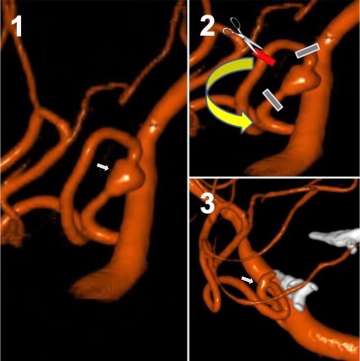

• Sequential images of aneurysm

Figure 6. Intrasaccular flow disruption of an ICA terminus aneurysm using the WEB device. Top panel demonstrates sequential images from left to right showing deployment and finally detachment of the WEB device

Intrasaccular flow disruption: This technique involves placement of a special braided mesh device (for example, the WEB device) inside the aneurysm in order to block blood flow into the aneurysm.  This technique is especially good for aneurysms located at branch points in the vessel, so called bifurcation aneurysms (Figure 6).